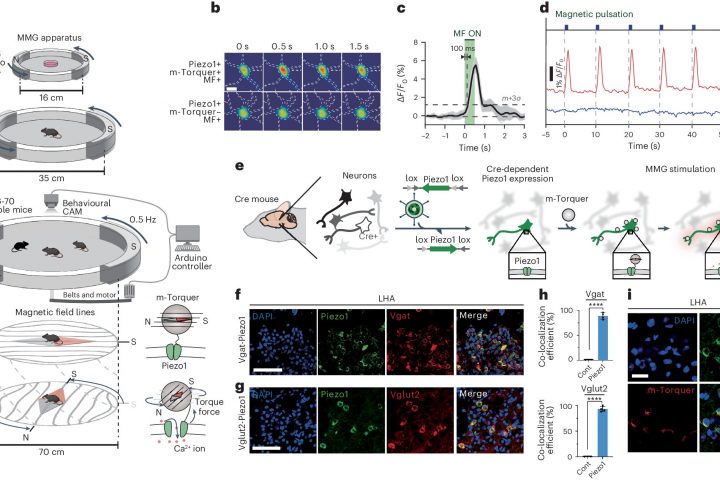

Researchers at the Center for Nanomedicine within the Institute for Basic Science (IBS) and Yonsei University in South Korea have unveiled a